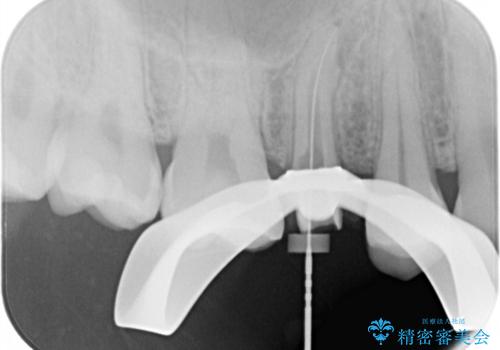

右上の被せものを除去したところ、中で歯が割れていたため、部分矯正で引っ張り出すことになりました。

歯を引っ張り出したり、歯肉の手術の経過待ちの間に、患者様のご希望で他の歯の虫歯治療も行いました。

・両どなりの歯に一時的にワイヤーを接着します。